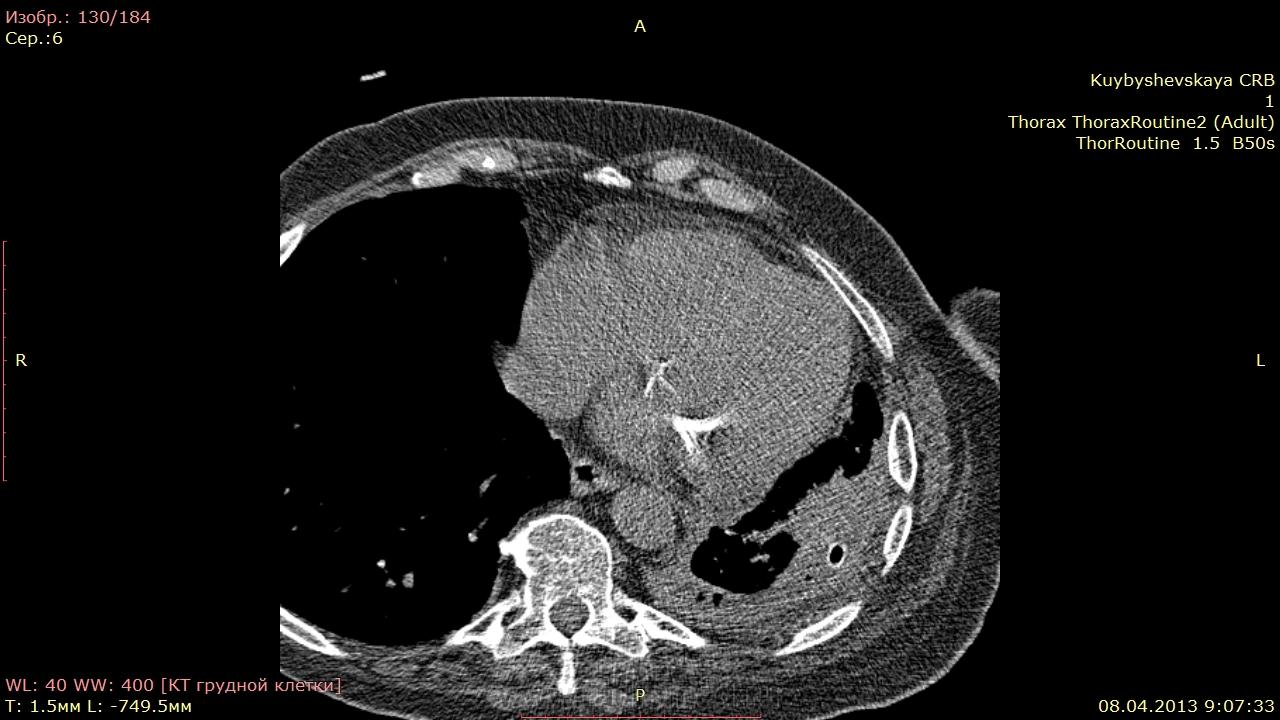

женщина 76 лет. 19 февралья поступила в терапевтическое отделение с диагнозом: внебольничная левостороняя s8-9 пневмония. после обследований гнойный осумкованный плеврит( отделяемое по дренажам, исследования) С середины марта субфебрильная температура. Сейчас опять в больнице. Отделяемое по дренажу гнойное. в пунктате признаки воспаления( атипии так понимаю не пишут) СОЭ-18 Leu -4.7. правильно ли думаем, что эмпиема?и в прикорневой зоне слева на контроле, может образование? ваше мнение.

контроль 08.04 DICOM http://files.mail.ru/ADBDE4F35AA844A7BCB26475A99D7AB3

скопление газа однозначный признак эмпиемы